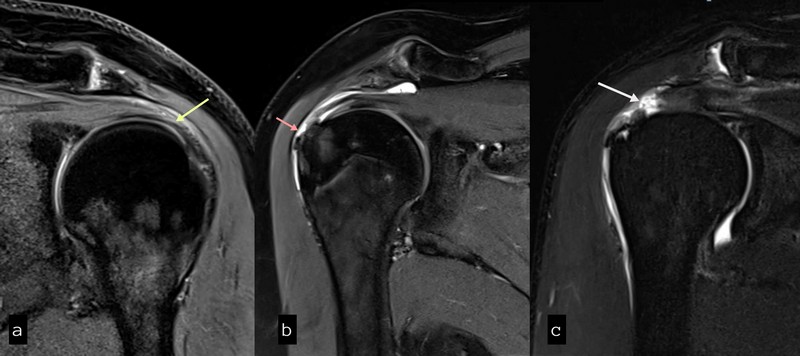

Η διάγνωση της ρήξης θα γίνει από έναν εξειδικευμένο ορθοπαιδικό χειρουργό με την κλινική εξέταση και θα επιβεβαιωθεί με τη βοήθεια μαγνητικής τομογραφίας , υπερηχογραφήματος και ακτινογραφιών, ώστε να αποκλειστούν άλλες πιθανές αιτίες του πόνου, όπως η οστεοαρθρίτιδα ή παθήσεις που ο πόνος αντανακλά στον ώμο, όπως παθήσεις του θώρακα και της καρδιάς ή αυχενική δισκοπάθεια. Παράλληλα θα εντοπιστεί η παρουσία ή μη υγρού και επασβεστώσεων στην περιοχή.